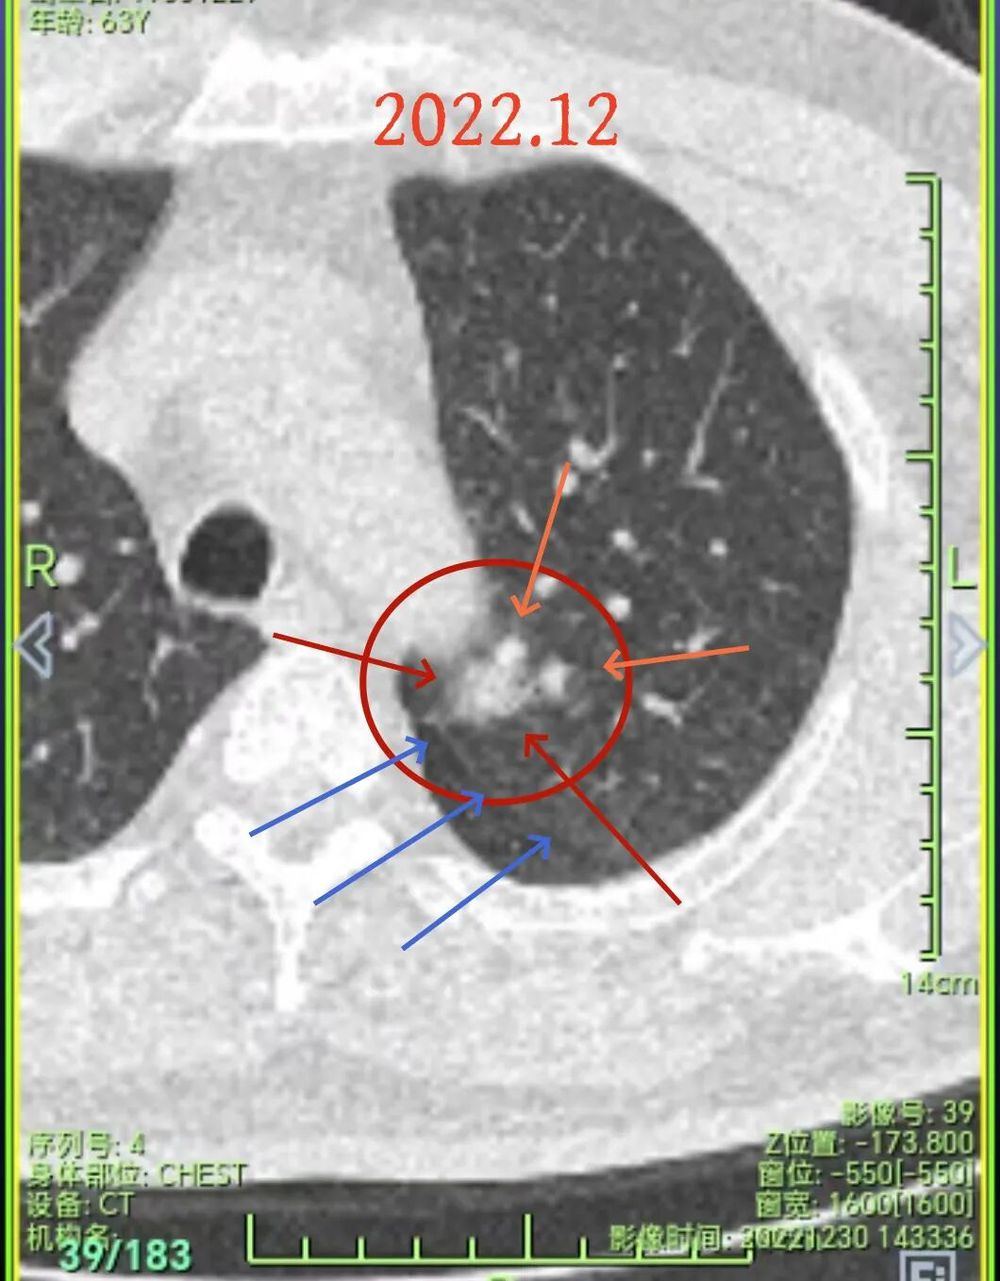

先看2022年12月时的影像:

这个片子质量较差,雪花点很多,清晰度不够。但这个病灶整体轮廓较清,密度不纯,贴近主动脉与叶间裂,灶内有细小空泡征,是要高度怀疑恶性,短期抗炎治疗后复查若无吸收好转,宜及时手术为稳妥。